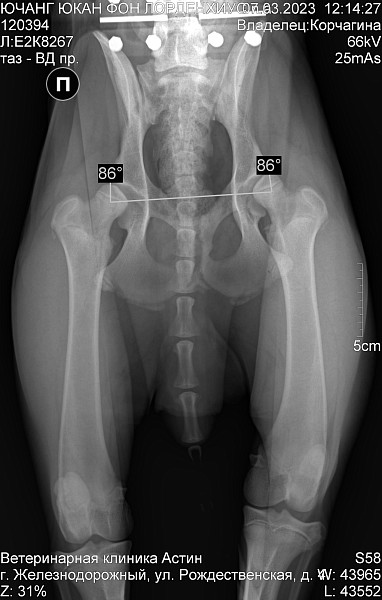

Немецкая овчарка. Кобель.

Др 29 07 2022

С первого дня дома бегал как заяц, на первых прогулках подтвердился такой бег. С трудом встаёт, перенося вес на передние лапы. Хромает спустя 10 минут прогулки.

Врачи в городе не дают внятных ответов и заключений. Хочется узнать имеется ли на снимке дисплазия?

Добрый день. Двустороння дисплазия тазобедренных суставов. Рекомендован прием ортопеда и имплантация суставов